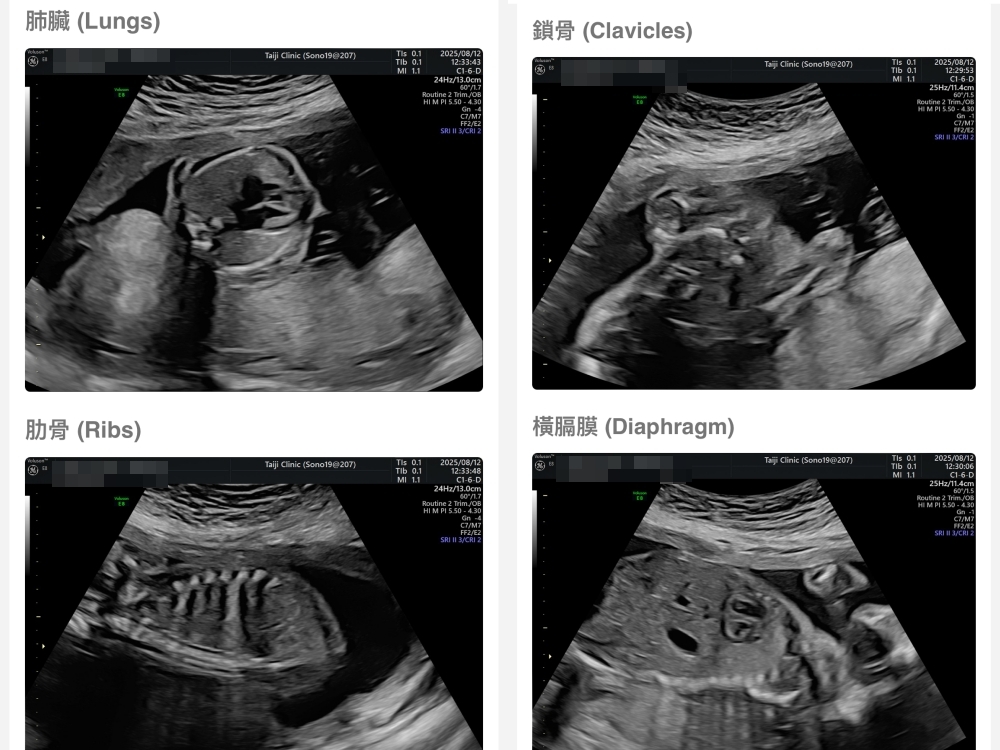

【台兒|高層次超音波|檢查結果】

▲離開診所後會收到MAIL,我們14:05離開,大約是16:45收到mail,裡面會有滿滿的超音波照片,紀錄的很詳細!也會提供紙本的報告,可以給日後產檢的醫師做參考👌